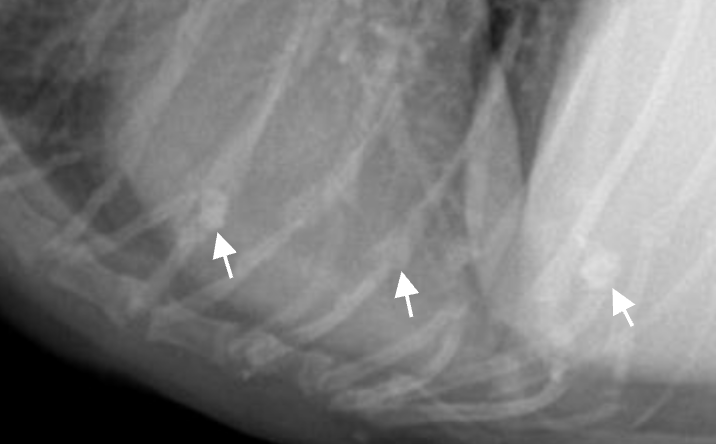

Pulmonary osseus metaplasia : 폐의 석회화 (노령성)![]() (폐전이에 비해 너무 작고, opacity가 bone에 더 가까움) |

==Knob sign== ![]() - 나이 많은 고양이에서 대동맥이 구불해지고, 심장이 누움. |